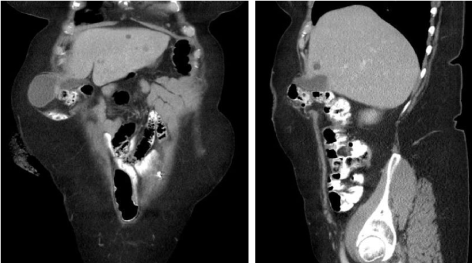

A 63-year-old white female with a complicated history following surgery for diverticular bleeding is referred for elective colostomy reversal. She had initially undergone a left colectomy with a distal transverse colon to sigmoid colon anastomosis; this was complicated by an anastomotic leak and left upper quadrant abscess, necessitating distal transverse colectomy and splenectomy, with creation of a right upper quadrant end transverse colostomy. A long Hartmann's pouch consisting of rectum and sigmoid colon was left in situ. At initial presentation, she complained of a large peristomal bulge and associated abdominal bloating. She denied abdominal pain with eating, nausea, or vomiting. Colonoscopy revealed only 18 cm of colon remaining from the colostomy to the cecum; the residual rectosigmoid stump measured 55 cm in length and was characterized by diffuse diverticular disease. A preoperative CT scan of the abdomen and pelvis demonstrated a large parastomal hernia with incarceration of the small bowel and gallbladder, as well as a midline fascial defect (Figure 1 and Figure 2). She subsequently underwent colostomy takedown with completion sigmoid colectomy, derotation of the right colon with an ascending colon-rectal anastomosis, cholecystectomy, appendectomy, and abdominal wall reconstruction at both the ostomy site and midline defect with on-lay bioprosthetic mesh. She had an uncomplicated post-operative course, and upon outpatient follow-up, she reported excellent bowel function without hernia recurrence.

Figure 2: a,b) Coronal and sagittal CT imaging showing herniation of gall bladder through a right upper quadrant parastomal hernia. View Figure 2